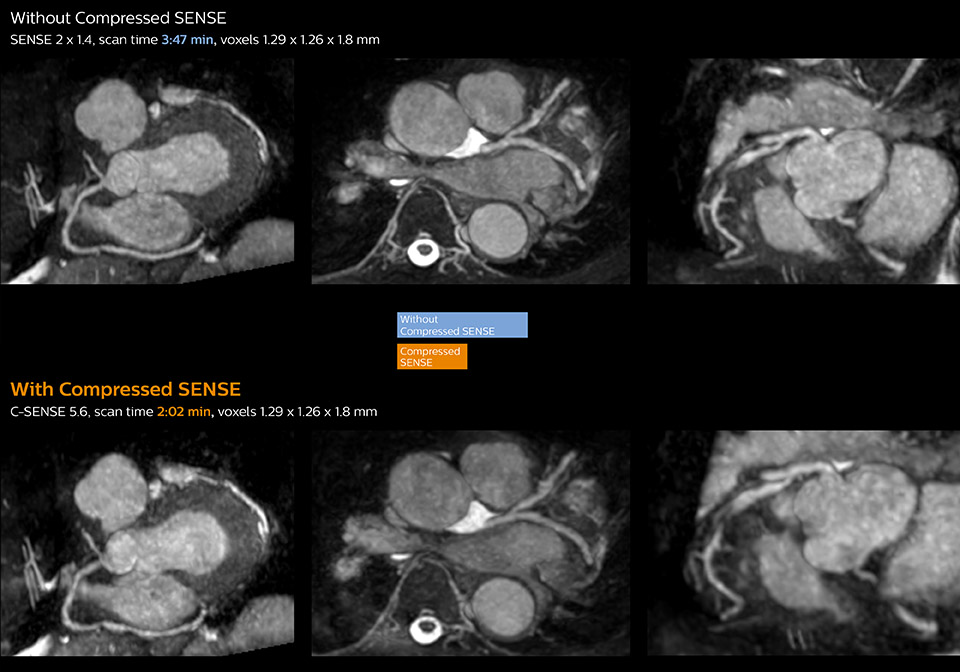

These images with and without Compressed SENSE were acquired on Ingenia 1.5T.